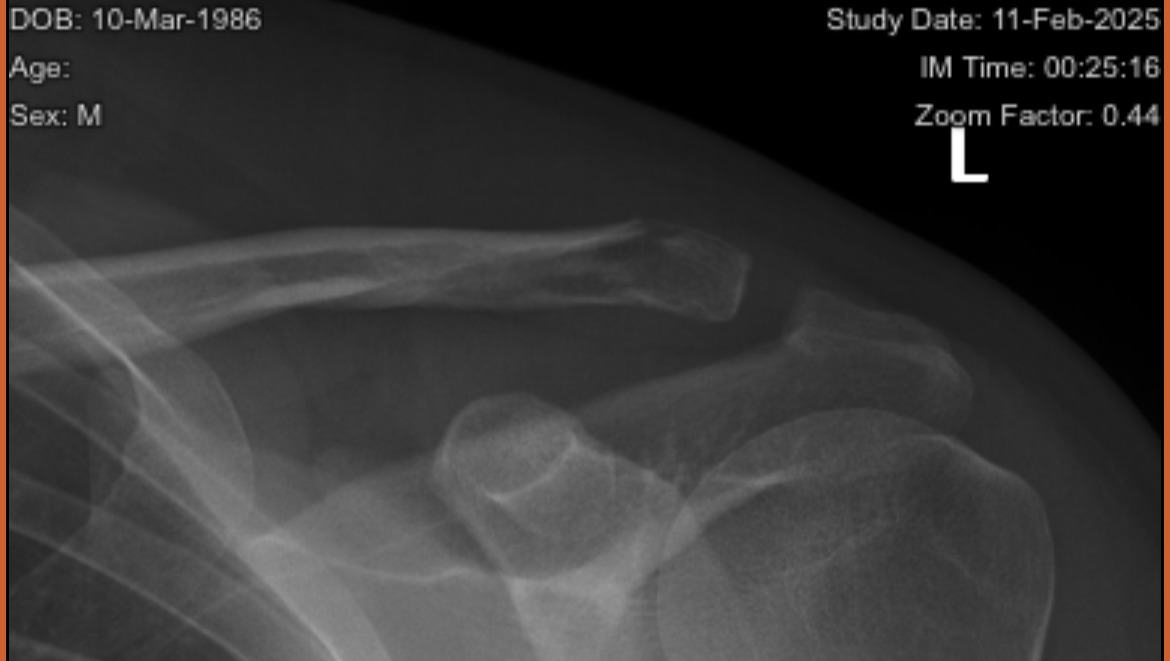

My housemate/good friend Karina got home a couple hours later after I went home from the Ebike crash and forced me to walk to ER, which is thankfully a block from our home. I got x-rays of my hip and shoulder as well as a CT scan of my head. It was confirmed that I had a concussion and a broken left clavicle. I am also left handed.

My first time in ER, I was told that I would have to wear a sling to immobilize my arm/shoulder and hopefully my clavicle would heal on it's own in 5-8 weeks. I was told to avoid screens & stick to activities that did not stress my brain.

I ended up at ER for the second time with my housemate. They did more head scans and x-rays. Thankfully, they said that nothing got damaged more than my first scans. I did end up with bruised ribs and abrasions on the other side of my head as a result of wearing the sling.

I have had a hell of a time getting in to see an orthopedic surgeon. I still don't know if I need surgery. I've gottne 4 referrals (one to an office that was closed, another to an office that doesn't take my insurance, another to an ORTHODONTIST and then the most recent). I wasn't functional for the first week due to the concussion.

It would be a huge help if y'all could throw some bones my way. I don't have an appointment with the orthopedic surgeon until March 12th and won't know until then if I need surgery or will need to cross my fingers and wear this sling for a lot longer.